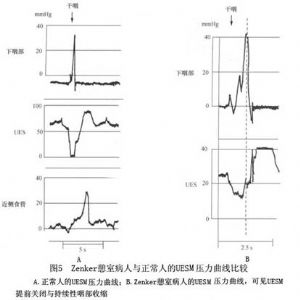

Cook等(1992)及Jamieson等(1994)對結構性病因中無法用神經性及肌源性疾病解釋的食管上括約肌功能紊亂合併咽食管憩室進行了深入的研究,他們發現在吞嚥過程中,咽食管憩室病人的食管上括約肌常提前關閉和處於持續性收縮狀態(圖5),下嚥部的食團內壓力明顯升高(圖6)。與此同時,他們測量了開放以後的括約肌的最大面積,發現病人的括約肌面積明顯小於正常人。

最近的研究工作發現Zenker憩室病人的食管上括約肌多有組織纖維化和括約肌炎症等侷限性肌病的組織學徵象,說明Zenker憩室的形成是食管上括約肌順應性降低和下嚥部食團內壓力升高以後,食管上括約肌在沒有解剖學的鬆弛狀態下,食團以高抵抗力長時期強力運行的結果。